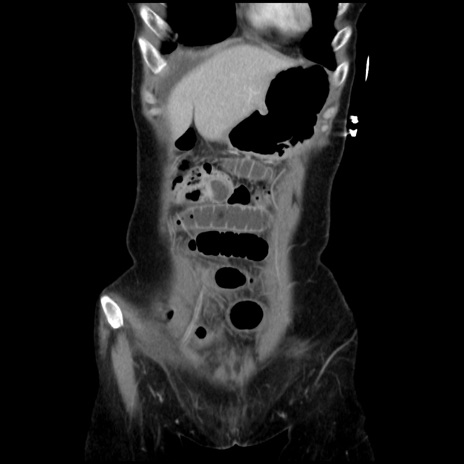

横断像

【症例】40歳代 女性

【主訴】上腹部痛、嘔気・嘔吐

【現病歴】約9時間前頃から急に上腹部痛、嘔気、嘔吐が出現。改善しないため救急要請。

【既往歴】子宮頚癌(広汎子宮全摘術、放射線療法)、腸閉塞

【身体所見】腹部:平坦、軟、腸雑音亢進、上腹部を中心に腹部全体に圧痛あり。

【データ】WBC 8400、CRP 0.03